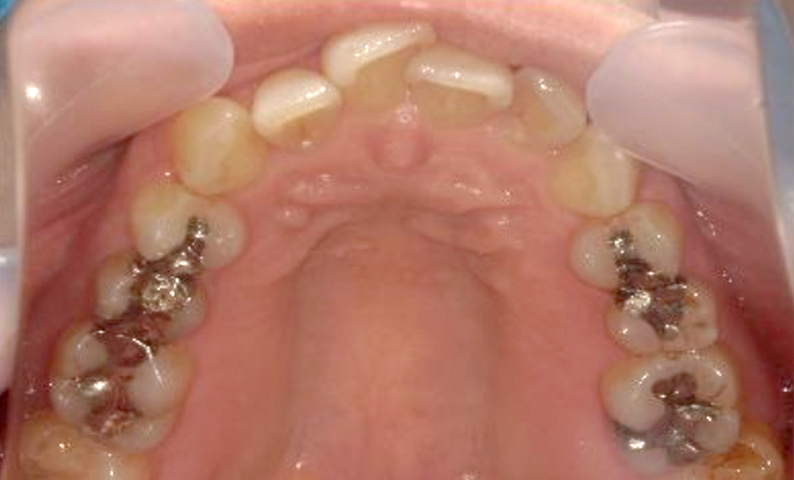

症例_003 上下顎の部分矯正

治療期間:12ヶ月金額:54万円+税男性八重歯前歯のガタガタ